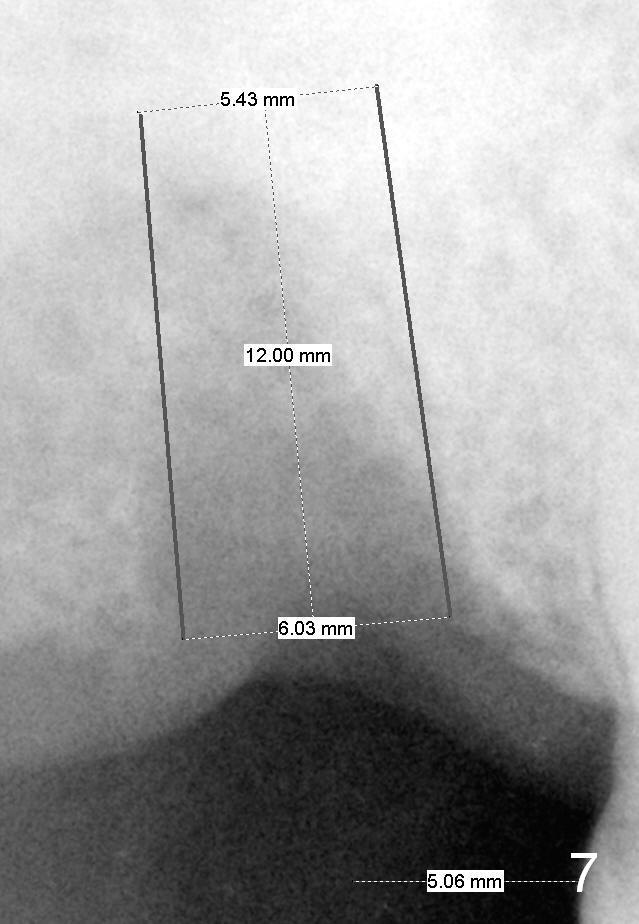

If the stability of the 5x14 mm tap is not sufficient, insert 6x14 mm tap. Extra wide implants will be tried, either 5.9 or 6.4x10 mm (SM, Fig.6) or 6 or 6.5x12 mm (UF, Fig.7). An immediate provisional may be fabricated.